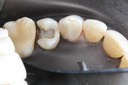

Alan Chinn #28 finish